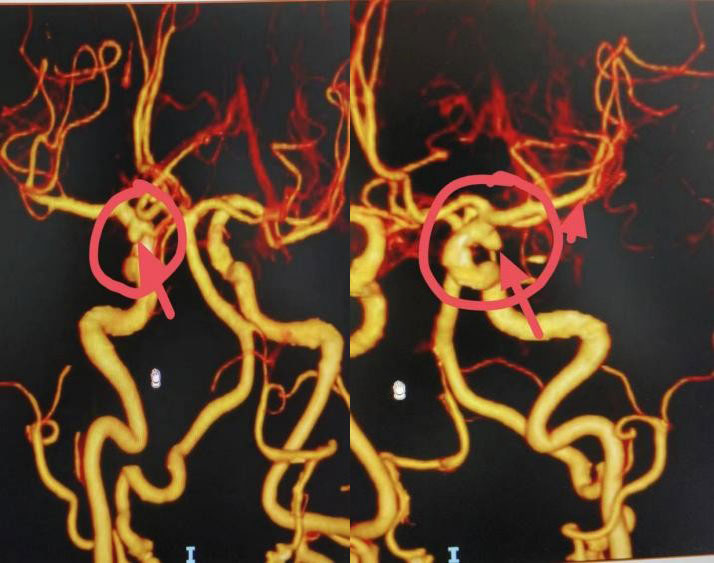

颅内动脉瘤的常见部位

首选筛查诊断方式为头部CT平扫,进而通过CTA、MRA、DSA确诊,其中DSA是诊断颅内动脉瘤的“金标准”。确诊评估后可选择开颅手术或微创介入治疗。